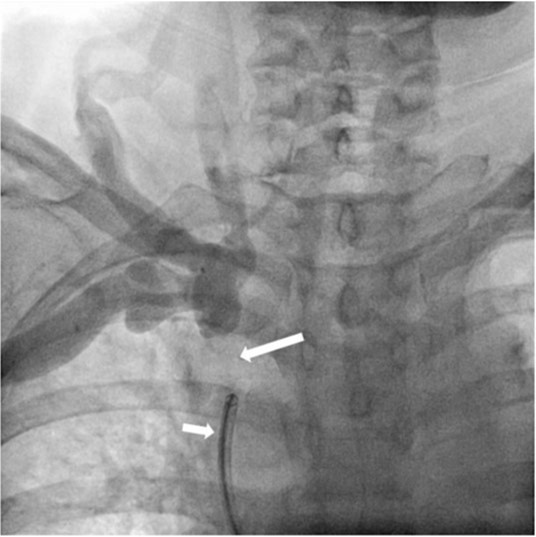

Fig. 2.

Fig 2. Venogramshows short segmental occlusion of right brachiocephalic vein (long arrow) and vascular sheath (short arrow) within SVC which was inserted via right common femoral vein.

초음파 유도 하에 우측 팔의 동정맥루 graft를 천자한 후 정맥조영술을 시행하여 우측 상완두정맥의 폐색을 확인함(Fig. 1). 5Fr Cobra 카테터(Cook, Bloomington, IN, USA)와 친수성 0.035 inch 유도철사(Terumo, Tokyo, Japan)로 폐색부위의 통과를 시도하였으나 실패함. 우측 대퇴정맥을 천자하고9Fr 65cm sheath (Arrow, Deutschland, Erding, Germany)를 상대정맥까지 진입시킨 후 5Fr Davis 카테터를 통해 약 2cm 길이의 상완두정맥 폐색 부위를 확인함(Fig. 2). Davis 카테터와유도철사로 상대정맥에서 우측 상완두정맥으로 통과를 시도함. 유도철사의 soft tip 부분으로 시도하였을 때 통과가 되지 않아서 반대쪽 hard tip 부분으로도 통과를 시도 하였으나 실패함(Fig.3). 유도 철사의 soft tip 과 hard tip 양쪽 모두 사용 하여 통과를 시도하였으나 막힌 부위의 위쪽 부분은 앞쪽(anterior side of the body) 을 향하고 있고 아래쪽 부분은 뒤쪽(posterior side of the body)를 향하고 있어서 천자 방향을 맞추기 어려웠음(Fig. 3). 우측 내경정맥을 천자하고 5Fr sheath를 삽입함. Sheath를 통해서 5FrKumpe 카테터와 0.035 inch 유도철사로 위에서 아래 방향으로 폐색부위 통과를 시도함. Hard tip으로 시술 도중 폐색혈관 주위로 유도 철사가 천자되어서 조영제의 누출이 있었으나 천자부위 주에 국한되어 있었고 임상적으로 문제 있는 혈류역학적 변화는 오지 않았음. Kumpe 카테터와 유도철사로는 천자 방향을 맞추기가 어려워서TIPS set (Cook, Bjaeverskov, Denmark)를 사용하기로 함. 천자된내 경정맥에 10Fr introducer sheath를 삽입하고 20G Colapinto needle을 폐색부위까지 진입시킴. 양쪽에서 정맥 조영술을 시행하여 폐색된 부위의 위치와 길이를 여러 각도에서 정확히 파악한 후, 폐색 부위를 천자함(Fig. 4). 천자 후 Colapinto needle을 통해 유도철사를 상대정맥에 진입시킴. 대퇴동맥을 통하여 삽입된 snare 카테터(ev3, Plymouth, MA, USA)를 이용하여 대퇴정맥 밖으로 유도철사를 빼냄(through and through technique)(Fig 5). 유도 철사만 통과된 상태에서 천자부 주위에 여러번의 천자로 인한 조영제 누출이 있었으나 주출된 조영제의 양이 적었으며 천자부 주위에 국한되어 있었음. Tractogram시행시 조영제의 누출은 보이지 않아서 유도 철사 주위에 국한 되어 있어서 풍선확장술을 시행 하기로 함(Fig. 6).대퇴 정맥을 통해 유도철사를 0.035 inch Amplatz wire(Cook, Bjaeverskov, Denmark)로 교체하여 내경정맥까지 진입시킨 후 풍선카테터 (Bard, NJ, US)를 삽입함.천자된 통로를 따라 직경 6 mm에서부터 16 mm까지의 풍선카테터로 차례대로 풍선확장술을 시행함(Fig. 7). 시술 후 정맥조영술에서 폐색부위는 개통되어 원활한 혈류를 보였음(Fig. 8). 시술 후에 오른쪽 팔의 종창은 호전됨.